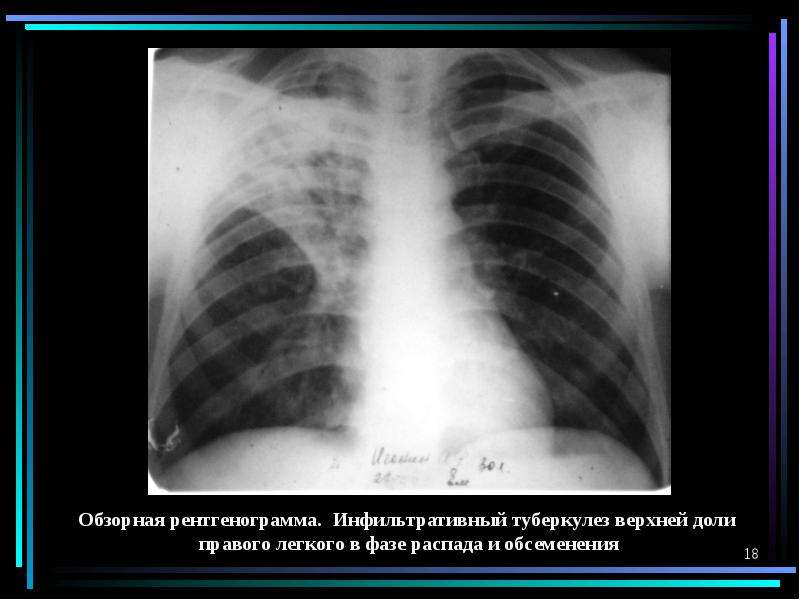

Иллюстрации по теме очагового и инфильтративного туберкулеза